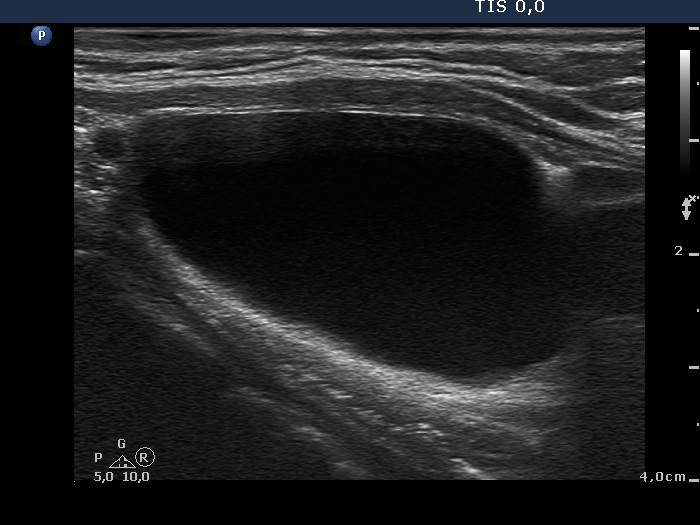

Ultrasonography. The thyroid was echonormal and contained a minimally hypoechogenic nodule in the ventral part of the right lobe. There was a cystic lesion under the lower pole of the left lobe.

Cytology of the thyroid lesion resulted in benign colloid goiter. 16 mL watery fluid was aspirated from the mass under the thyroid. Wash-out parathormone level of the cystic fluid was 917 pg/mL, while serum parathormone was 24.3 pg/mL (normal value: 15-65).

Final diagnoses. Benign thyroid nodule. Parathyroid cystadenoma.